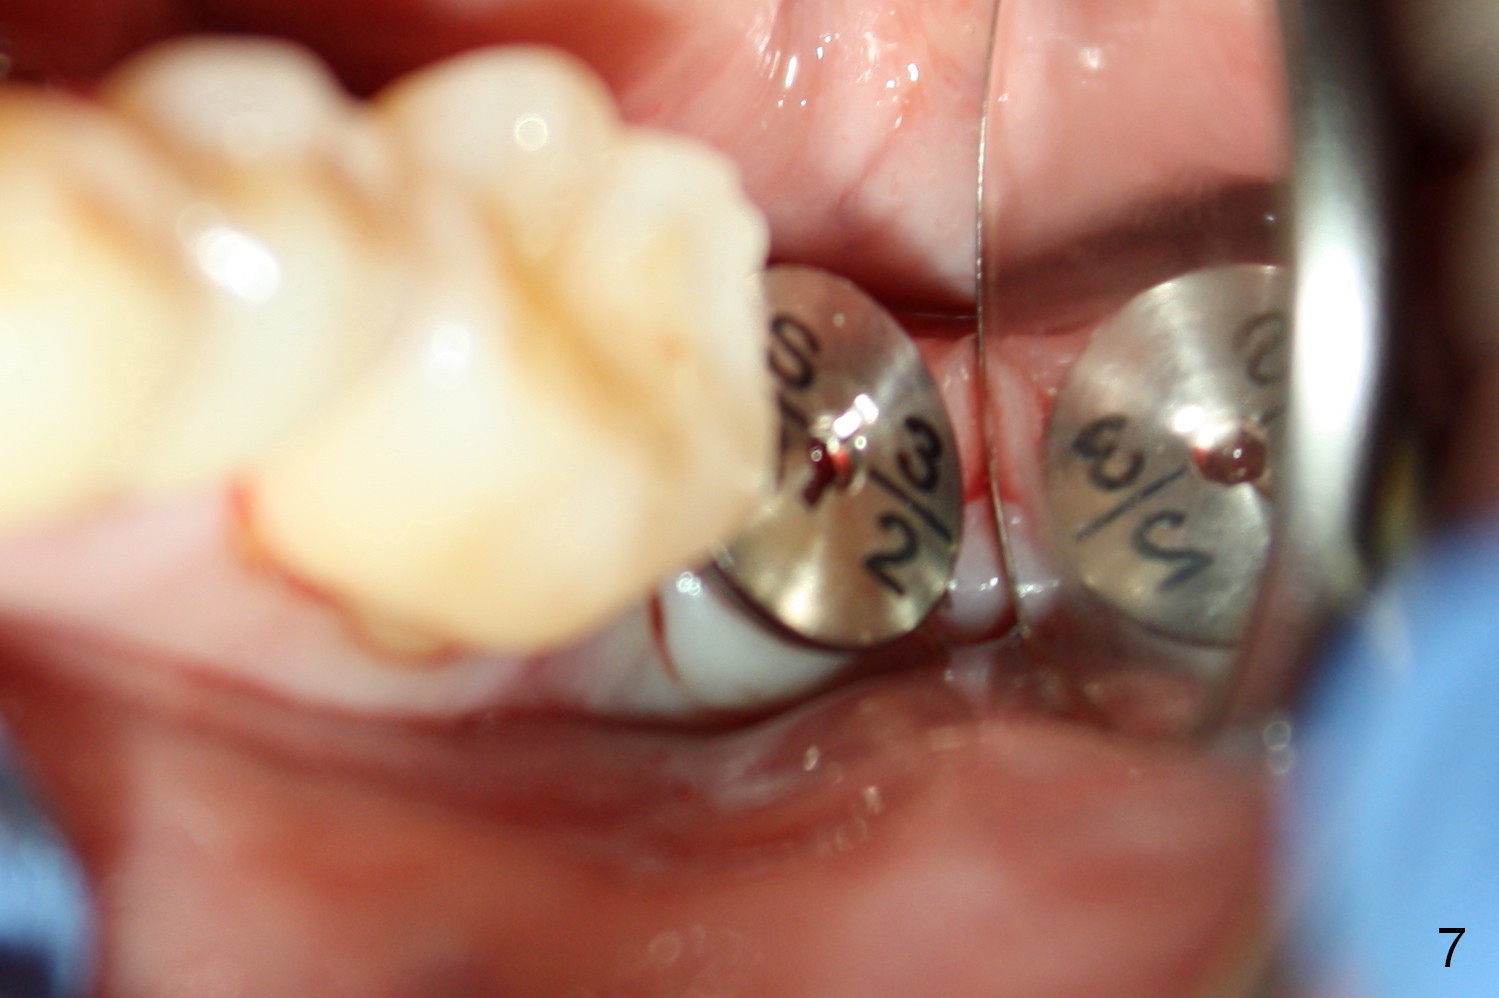

A 48-year-old lady is a dental phobic, requesting extraction of the lower left 2nd molar (Fig.1). She returns for implant placement 9 months post extraction (Fig.2). The ridge is mildly to moderately atrophic. It appears that a 5x12 mm implant is appropriate for the site (Fig.3). For safety, osteotomy is initiated at the depth of 10 mm; it appears that there is enough height for a 12 mm implant (Fig.4). The depth is controlled by drill stopper (Fig.5 S). Finally a 5x12 mm implant is apparently safely placed (Fig.6). A healing abutment is placed and the incision is sutured with 4-0 Chromic gut (Fig.7). Perio dressing is applied around the healing abutment for wound protection (Fig.8). It appears that the healing abutment (Fig.8': *) helps stabilize the perio dressing, which remains in place 1 week postop. When the perio dressing is removed, the wound around the healing abutment is healing (Fig.9). There is no bone loss around the implant 3 months postop (Fig.10 (H: healing abutment), or 16 months postop (i.e., 9 months post cementation, Fig.11,12). The patient complains of pain when she chews with the implant crown, but pain stops whenever she does not bite. Percussion does not elicit any discomfort. The gingiva is healthy. There is possibility of the buccal plate being thin or the lingual plate being perforated in the submandibular fossa. If the discomfort remains the same next 6 months, CBCT will be prescribed.